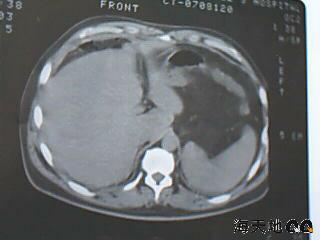

男 32y 外伤后一月余,现 t38.5,肝区隐痛。

右肝膈顶区液气平面.右膈肌增厚改变,病灶下部层面呈半月形延伸于肝表面.且于横结肠无明确密度切关系.

结合临床症状;考虑膈下脓肿.建议薄层矢状重建进一步证实.

鉴别;1,膈疝;2,间位结肠.

右隔肌与肝顶之间隙有长气液平,其下散在点状气体影,右侧腹膜局限增厚。考虑右膈下脓肿。

考虑右膈下脓肿。病灶不在肝内,位于肝外膈下;病灶下方的层面无结肠影与之相连。

右膈肌增厚,肝膈间见条状低密度影内可见积气影及宽大液平面,并未见与结肠相连。因此考虑膈下脓肿。